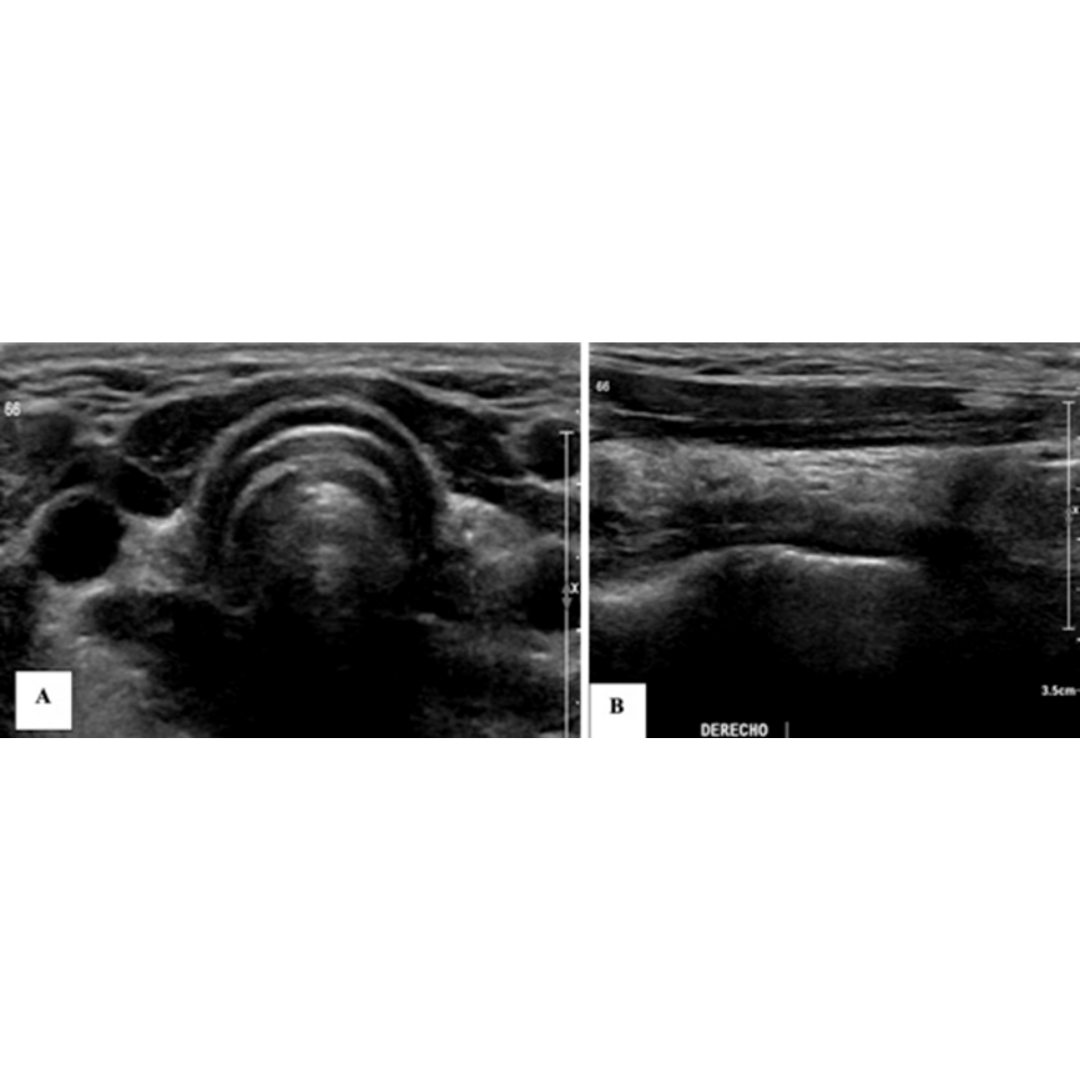

Figura 4. Hematoma post quirúrgico, por linfadenectomía izquierda, imagen (a) se observa corte longitudinal y en imagen (b) corte transversal a nivel del segmento cervical III.